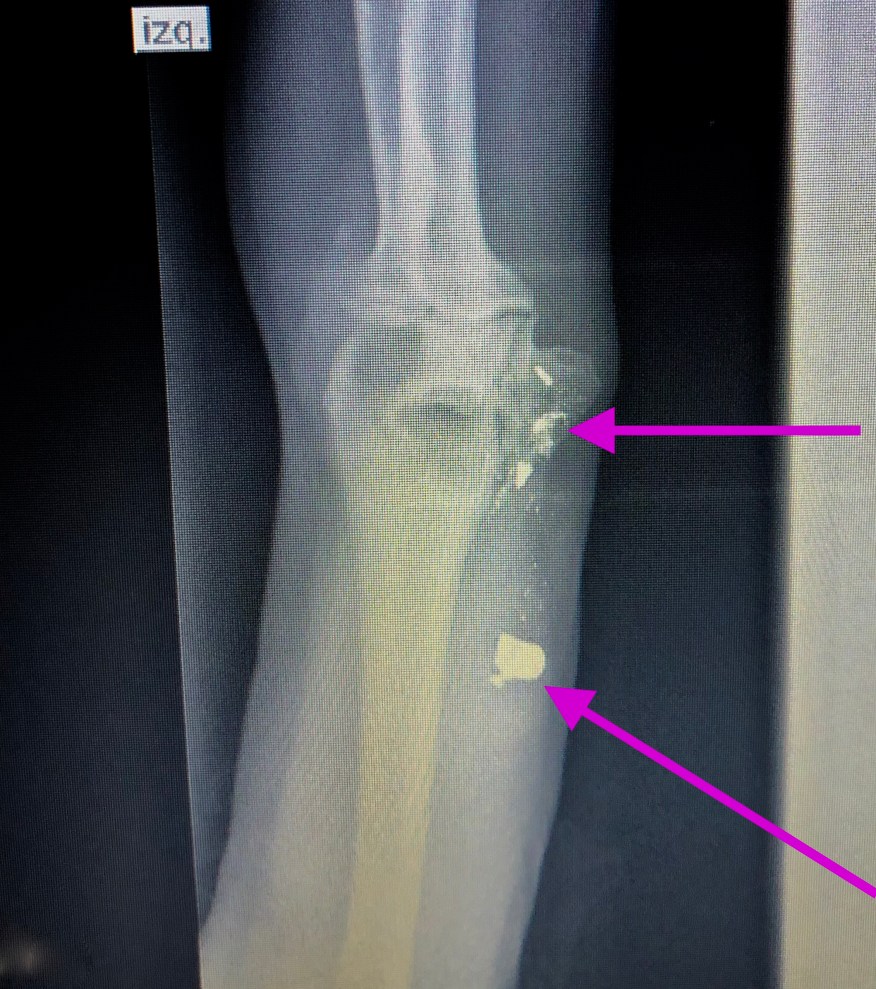

Moe (not his real name) 53, tells me he was sitting in his home this past December when a bullet tore through his elbow, fracturing it. The bullet wasn’t intended for him, but bullets have a funny way of traveling a long ways before they stop. He eventually discovered who did it, but says he didn’t want to have anything to do with this person, so he didn’t pursue any retribution. We are trying to regain some of his function now, but he does have some nerve damage unfortunately.

Bullet fragments pink arrows.